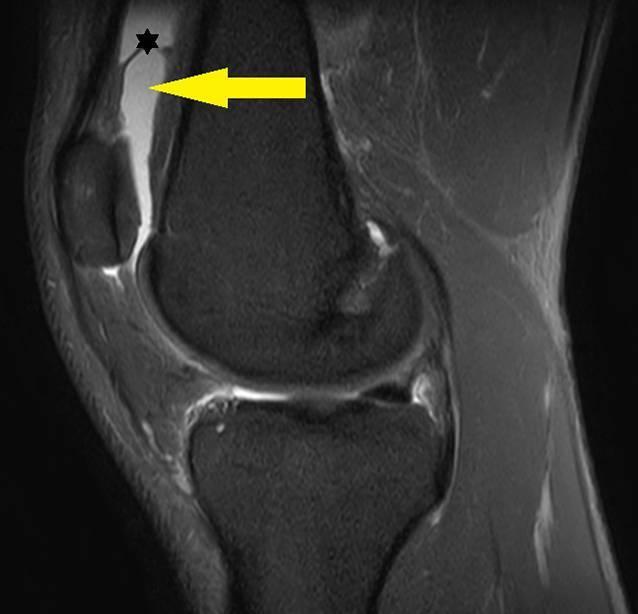

https://cdn.ncbi.nlm.nih.gov/pmc/blobs/5b6c/7925465/319b2f23a497/132_2020_3935_Fig1_HTML.jpg